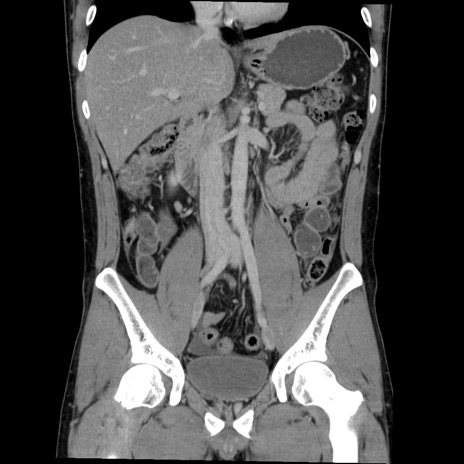

症例36(冠状断像)

【症例】20歳代 男性

【主訴】心窩部痛

【現病歴】今朝より上腹部痛あり。一旦軽快していたが再度出現したため救急要請。昨日夕に白身の魚を含む刺身を食べた。

【身体所見】BP 136/89mmHg、HR 74/min、BT 37.0℃、腹部:膨満、軟、心窩部に圧痛あり。反跳痛なし、筋性防御なし、腸雑音やや亢進あり。

【データ】WBC 17700、CRP 0.48